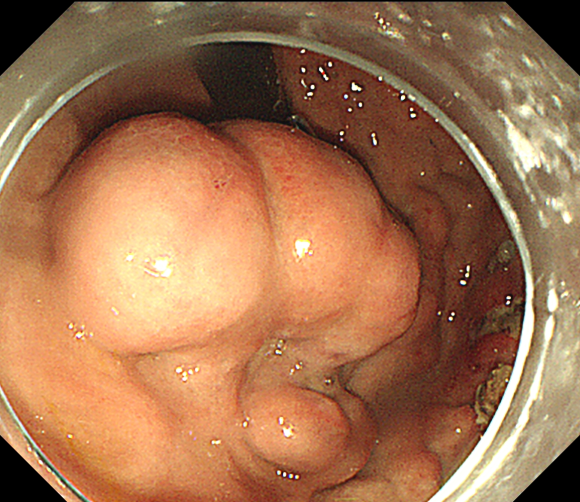

孤立性胃底巨大曲张静脉

接受手术的患者因急性消化道大出血,被送至北京清华长庚医院急诊科,反复发作的大出血伴随着失血性休克像一颗“定时炸弹”时刻威胁着患者的生命。胃镜检查的结果显示出血是由孤立性胃底巨大曲张静脉引起,此时此刻,只有完全封堵曲张静脉才有可能从根本上解决问题。